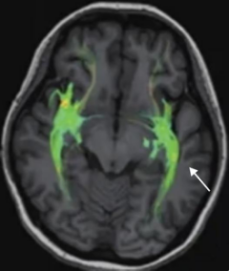

弥散张量成像(DTI): 这是更前沿的技术。它能直观地显示神经纤维束的走向和完整性。DAI患者的纤维束会出现中断、稀疏、走形紊乱,就像高速公路被多处截断。

图片说明:女,26Y,DTI示左侧丘脑、脑干区白质纤维束明显减少(白色箭头所示)。